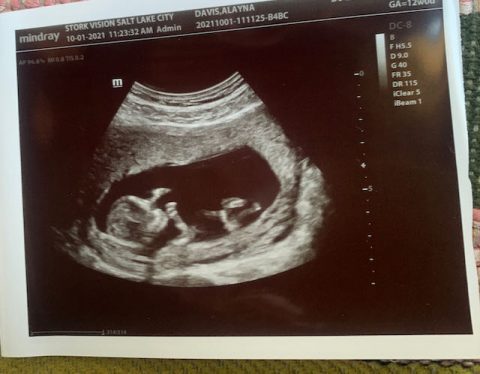

They decided to get married in Austin, and we got to work planning a ceremony at our ranch that would take place at 8AM Sunday morning, September 19th. We had about 12 days to get the ranch ready and make all the wedding plans. By the time Alayna and Choi flew in to Austin on the 17th, we were just about ready and so excited! Imagine a bottle of champagne that’s been shaken-that was us. Then Alayna and Choi gave us this happy news.

Alayna told us she was ten weeks pregnant and we exploded in a joyful, crying, hugging, high-fiving fizz of celebration. We decided to keep it a secret from our families until after Nate and Jo got married and drove off Sunday afternoon. After a full day Saturday getting everything ready, we gathered that night for barbeque down the road with all the families. Nate and Jo seemed amazingly calm and so, so happy.